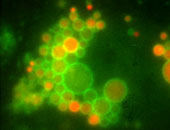

David Teis konnte am IMP, dem Grundlagenforschungsinstitut von Boehringer Ingelheim, einen solchen Komplex an menschlichen Tumorzellen identifizieren. Er besteht aus den Eiweißmolekülen p14 und MP1, sowie zwei Enzymen aus der Gruppe der MAP-Kinasen. Dieser Komplex ist an einer bestimmten Struktur innerhalb der Zelle, dem sogenannten Endosom, aufgehängt.